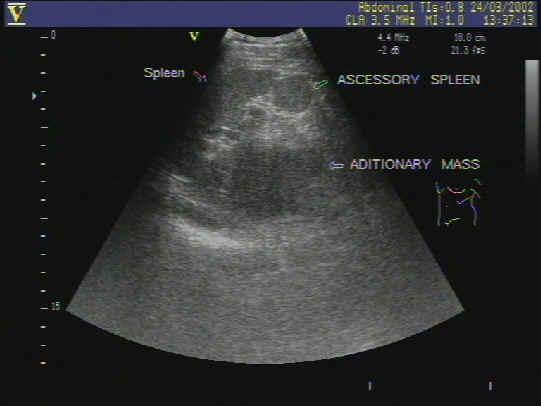

副脾的超声表现图片

副脾彩超图片

副脾超声图片

脾脏和副脾图片